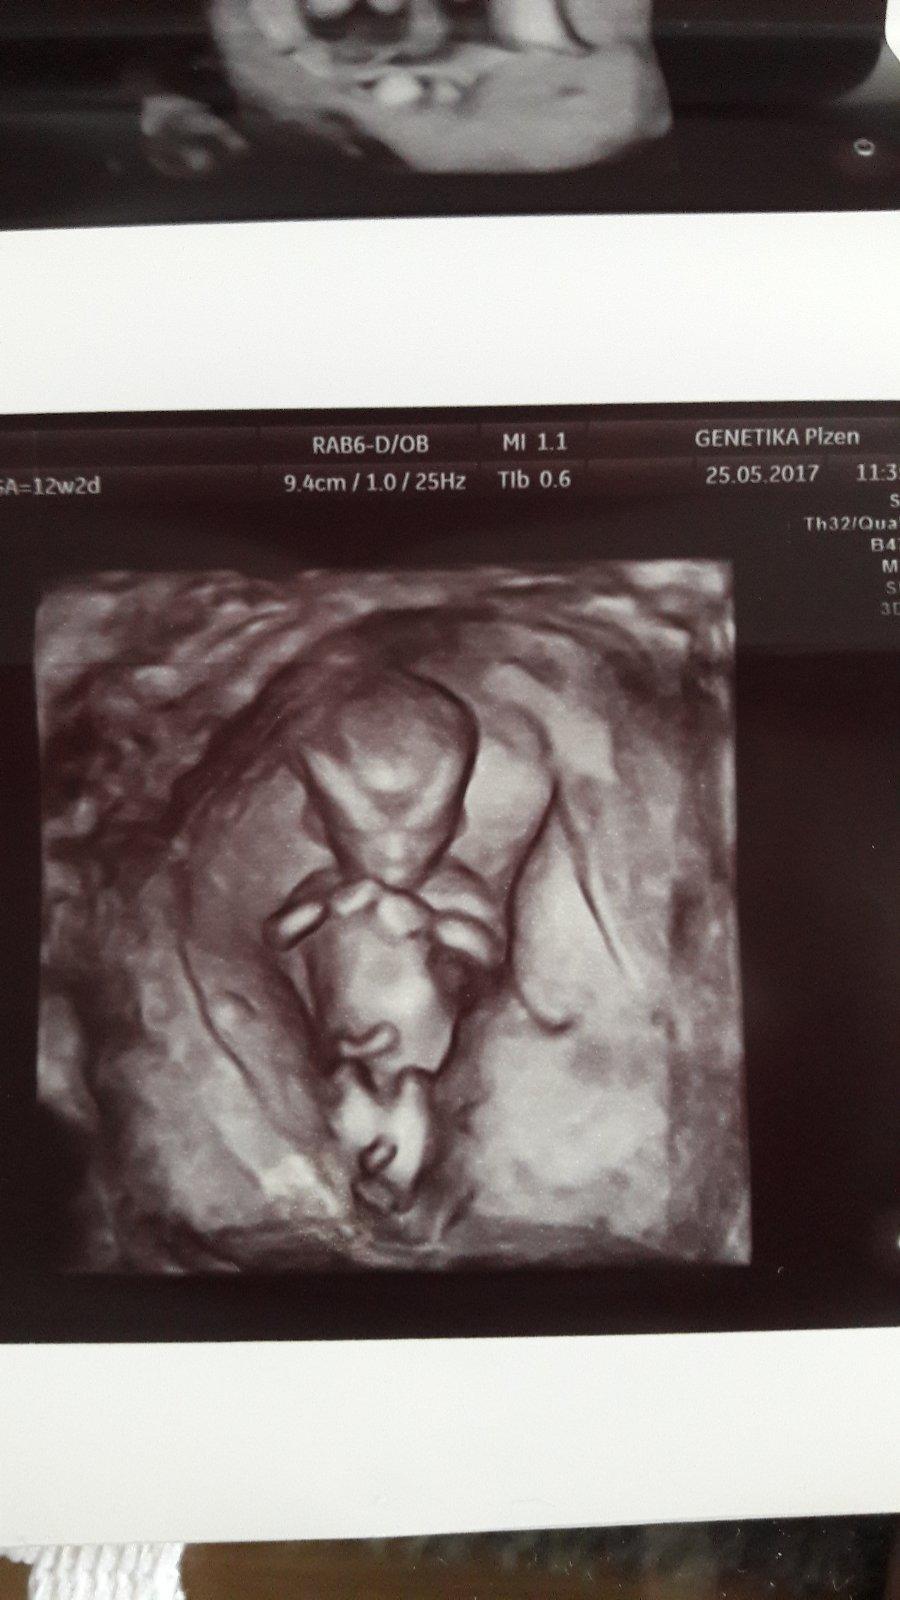

jinak sem si trosku hrala.

Nase princeznicka...asi...😀